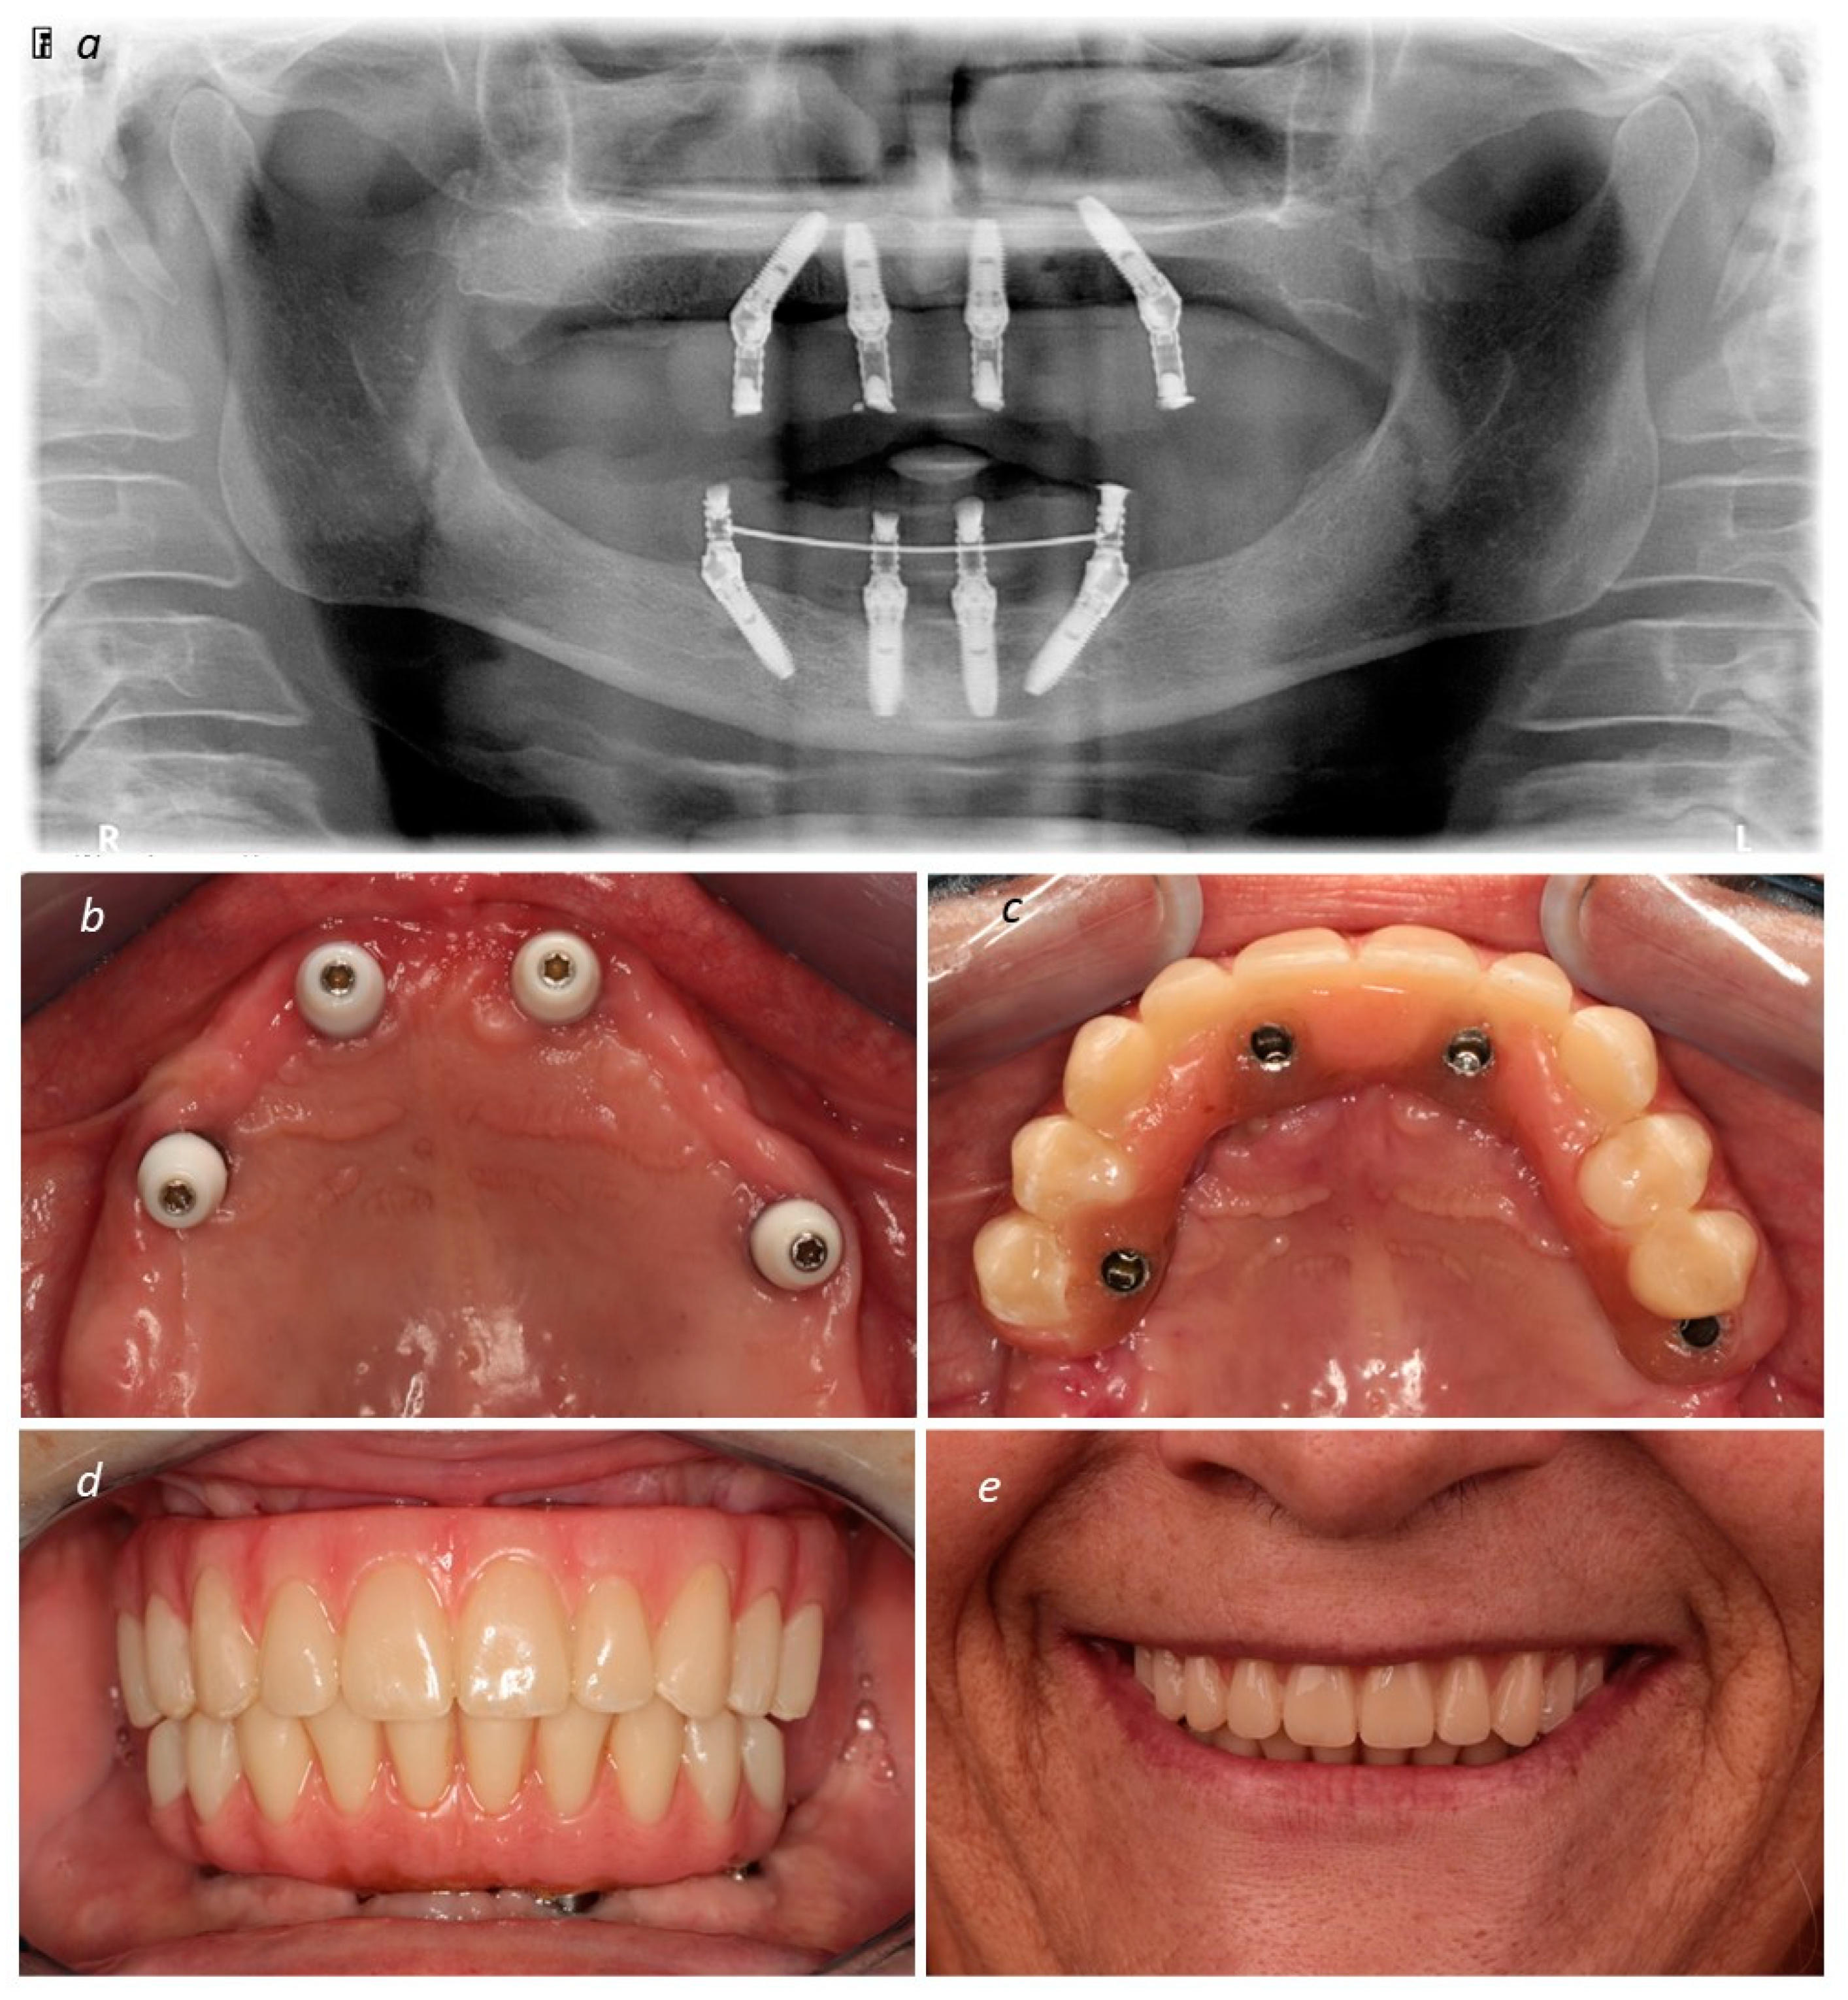

Description of the Technique

3. Results